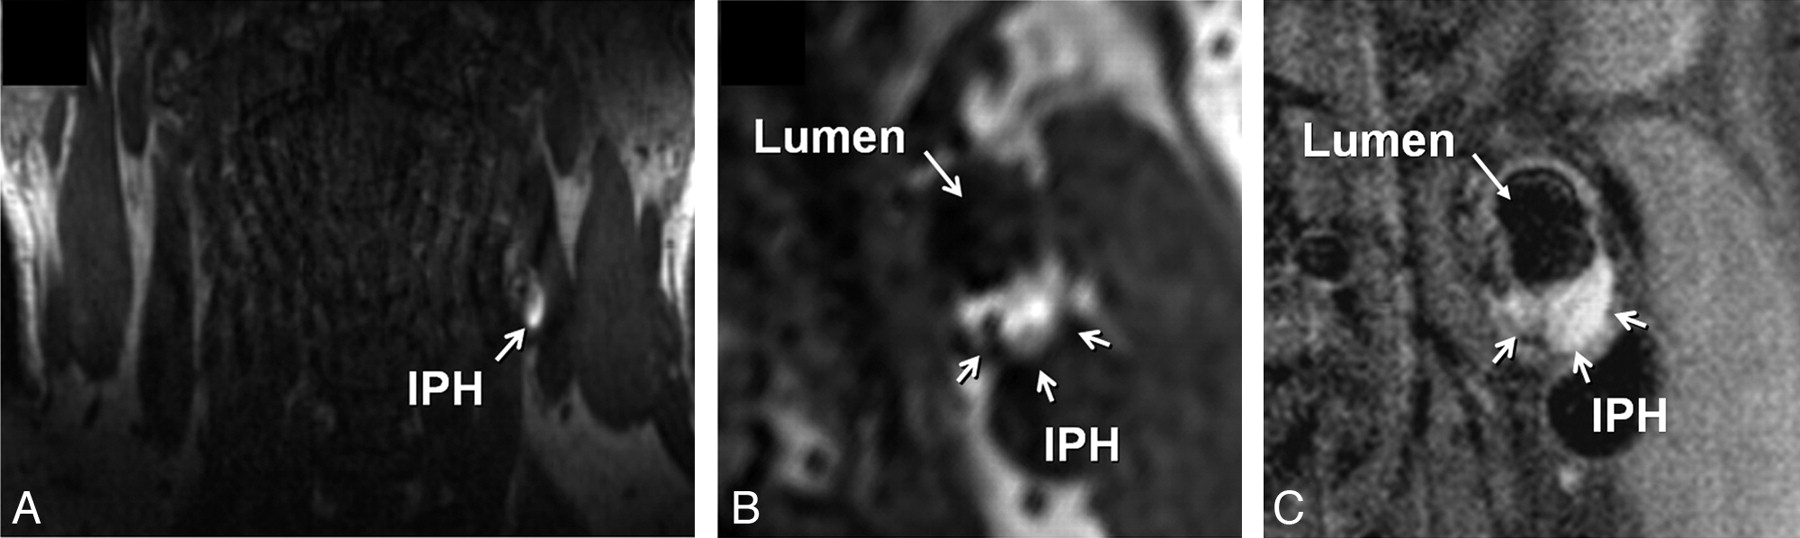

IPH was identified, by using established criteria, as hyperintense on heavily T1-weighted gradient-echo images (ie, CE-MRA mask images) (Fig 1).17,18 Adventitial enhancement was categorized as a marker of neovascularity on the basis of postcontrast BBMRI images by using the corresponding precontrast series for reference. Adventitial enhancement categories were determined by visual estimation of the percentage of involvement of the outer wall circumference (ie, adventitia) for the section showing the thickest plaque as follows: 0, no enhancement; 1, enhancement of <50% of the outer wall circumference; and 2, enhancement of ≥50% of the outer wall circumference (Fig 2). Carotid stenosis was measured by an attending neuroradiologist (B.A.W.) according to the NASCET guidelines based on the TOF MRA.19,20

Identification of IPH in the left carotid artery of a 60-year-old man with an ipsilateral cerebrovascular ischemic event. A, Source image from the coronally oriented CE-MRA mask sequence shows hyperintense signal intensity in the left carotid artery wall corresponding to IPH. The high signal intensity is seen on the transverse view of the mask image (B) reconstructed in the same plane as the T1-weighted precontrast BBMRI (C).